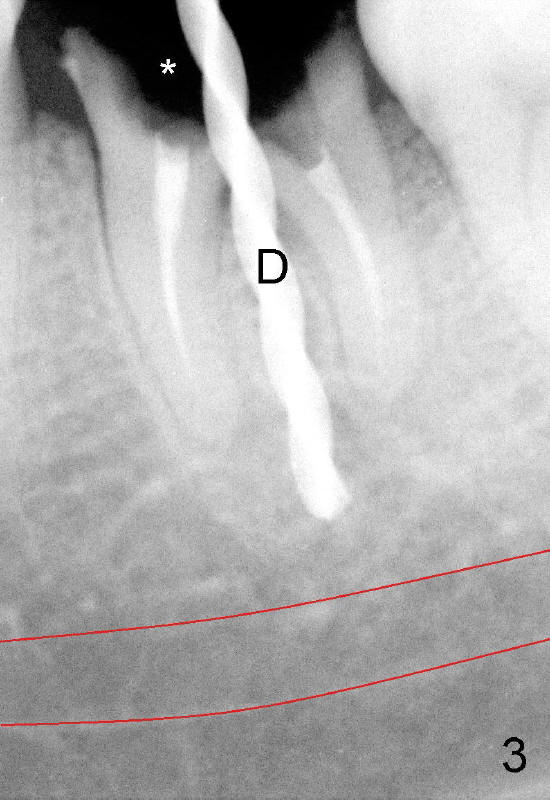

A 41-year-old lady fractures the crown of the lower left 1st molar (Fig.1.2). After removal of the remaining crown (Fig.3*) and exposure of the top of the septum, a pilot drill (D, 1.5 mm) is used to initiate the osteotomy. Drills with increasing diameters could be used to enlarge the osteotomy while the roots are in place (Fig.4: white rectangular outline).